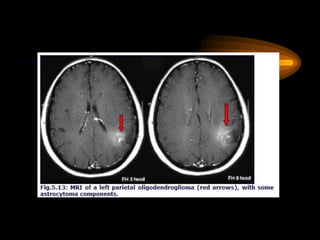

Oligodendroglioma

• Tienen un curso más benigno y

responden al tratamiento mejor

que los astrocitomas. Derivan de

la oligodendroglía.

• Localización: Es

fundamentalmente supratentorial.

• Anatomía patológica: Células

en “huevo frito”. Son los que más

se calcifican y los que más

cursan con convulsiones. La

supervivencia a los 5 años es

mayor al 50%.

Oligodendroglioma • Tienen uncurso más benigno y responden al tratamiento mejor que los astrocitomas. Derivan de la oligodendroglía. • Localización: Es fundamentalmente supratentorial. • Anatomía patológica: Células en “huevo frito”. Son los que más se calcifican y los que más cursan con convulsiones. La supervivencia a los 5 años es mayor al 50%.